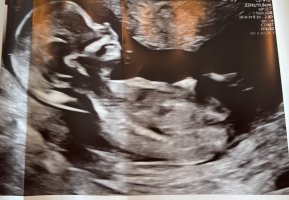

Gjette kjønn fra tidlig ultralyd. Nub teorien.

Hei. Er ny her :-) Var på tidlig ultralyd i dag. Uke 14 (13+ 0). Klarer noen å gjette om det er gutt eller jente?